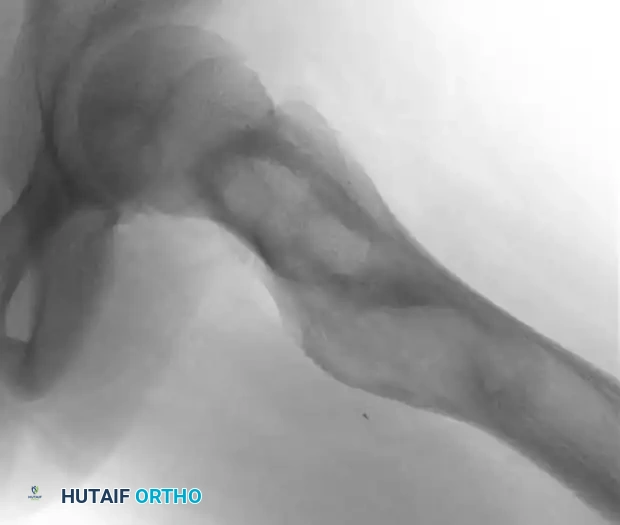

The radiographic signature of fibrous dysplasia is a radiolucent, expansile lesion with a characteristic granular, "ground-glass" matrix.

Fig. 20-10 A and B: Left hip of a 12-year-old girl demonstrating the classic ground-glass appearance and expansile nature of fibrous dysplasia.